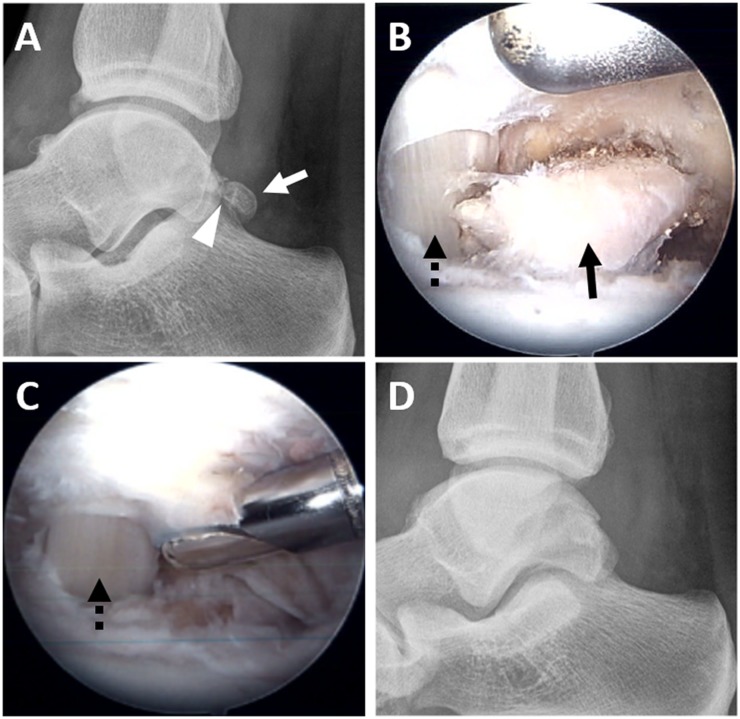

与其他撞击综合征一样,一线治疗是保守措施。如果这些措施失败,则手术仍是可行的选择(图15)。最近的一项荟萃分析比较开放式和关节镜下治疗没有发现病人满意度的变化。然而,值得注意的是,接受关节镜治疗的患者并发症较少(15.9%对7.3%),尤其是主要并发症较少(13.8%对5.4%)。大多数患者平均在8周或16周内通过关节镜和开放手术技术恢复到完全活动状态。

图15。

一位25岁的专业曲棍球运动员有后撞击:(A)术前侧位片显示三角肌(白色箭头)合并软骨退化(箭头)。(b) 软组织清创后的关节镜图像显示暴露的os三角(黑色箭头),内侧可见拇长屈肌腱(FHL)(黑色虚线箭头)。(c) 关节镜下切除os三角后的影像,FHL在内侧可见(黑色虚线箭头)。(d) 术后的侧位片证实手术成功。